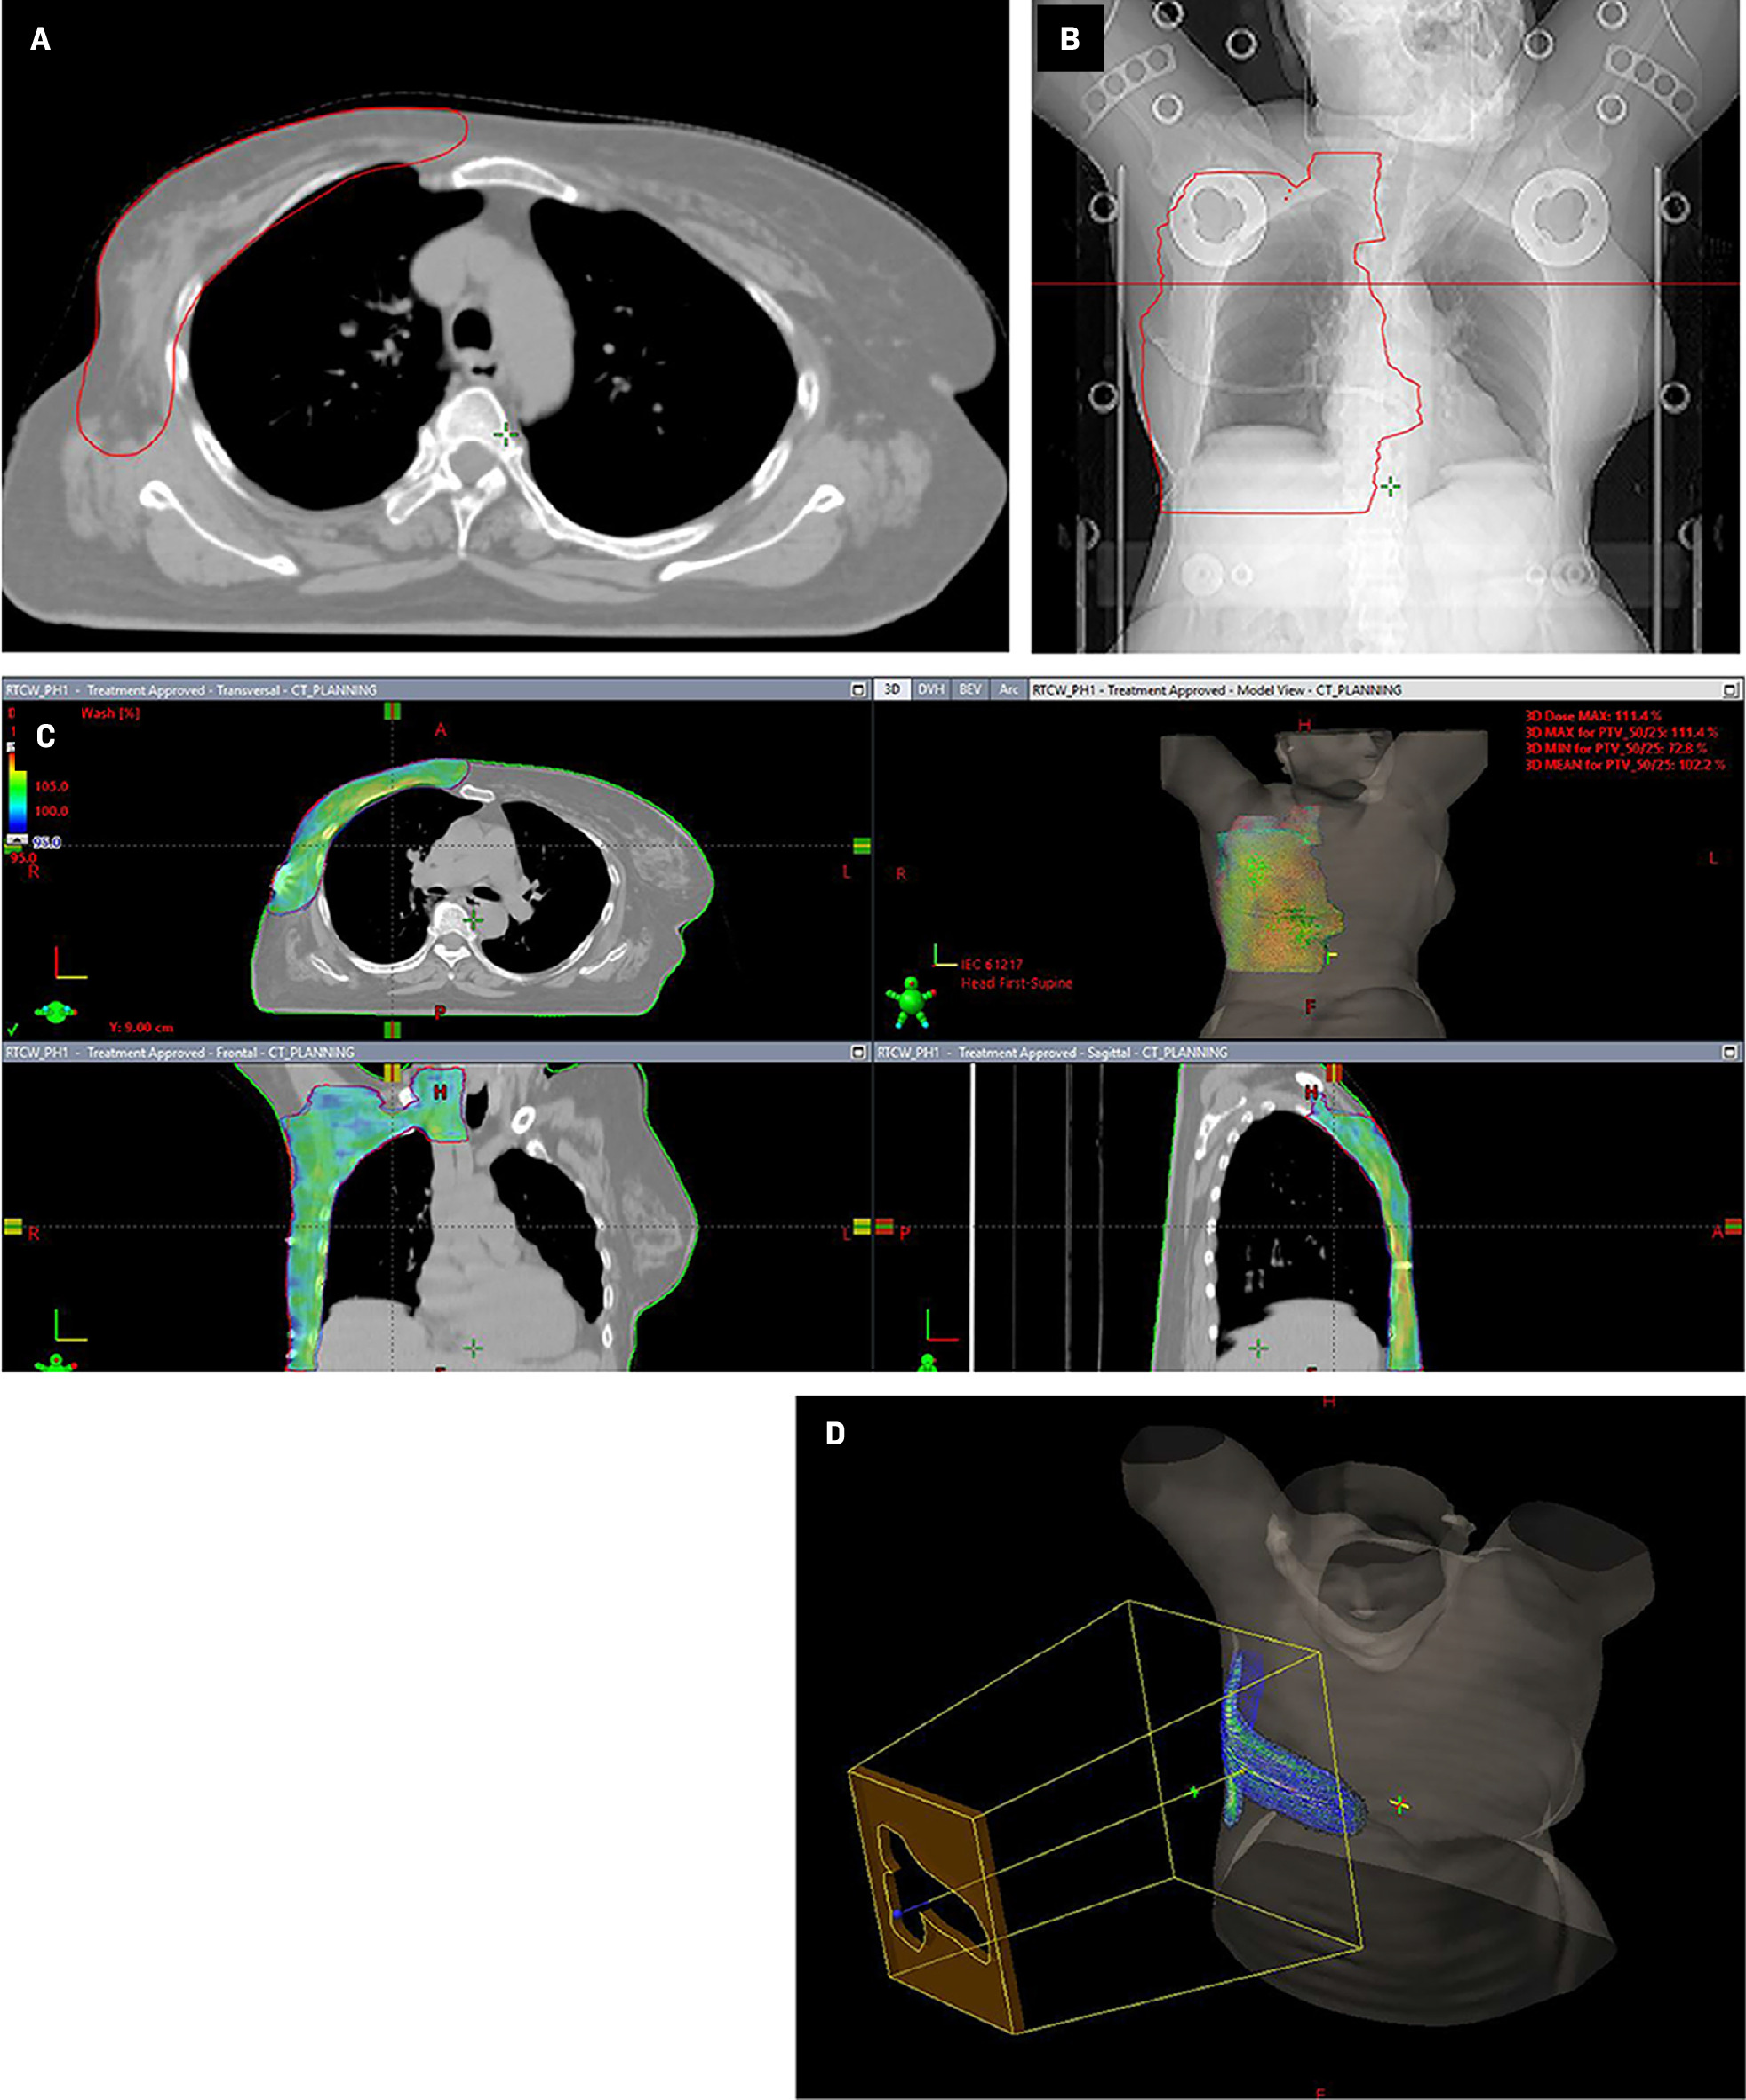

In view of the locally advanced nature of the primary tumor and presence of high-risk pathological features (large tumor size, LVSI, and nodal involvement), the patient received adjuvant locoregional radiation therapy (Figure 2). The internal mammary node region was not included in the field of radiation as there was no radiological evidence of disease or data showing any significant benefit to using this treatment for sweat gland carcinoma of the breast.

Radiation therapy dose prescription:

Phase 1: Planning treatment volume (PTV), which includes the chest wall, axilla, and supraclavicular nodal region, 50 Gy in 25 fractions, 2 Gy per fraction, with the TrueBeam (Varian) linear accelerator using 6 MV photons with the RapidArc technique. A 5-mm gel bolus material was used to cover the chest wall target region (including the surgical scar and drain site) to have adequate radiation dose buildup over the skin of the chest wall.

Phase 2: PTV boost, which includes the chest wall surgical scar and drain site, of 10 Gy in 5 fractions, 2 Gy per fraction with 6 MeV electrons.